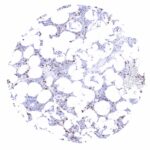

| Genitourinary | Kidney | Strong membranous CD35 positivity of visceral (podocytes) and peripheral cells of the Bowman capsule. |